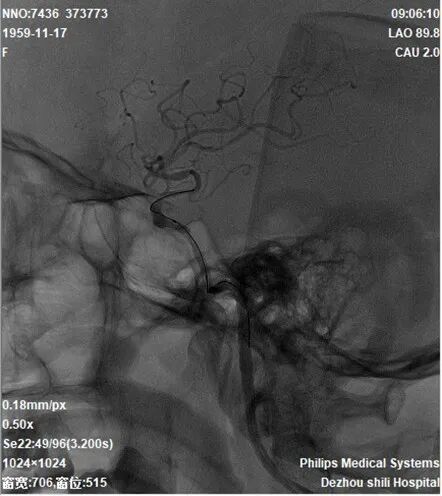

2022-7-20 颅脑CTP

重要影像结论:右侧放射冠区新发脑梗死,右侧颈内海绵窦段重度狭窄,右侧大脑半球缺血。

重要影像结论:右侧大脑半球缺血。